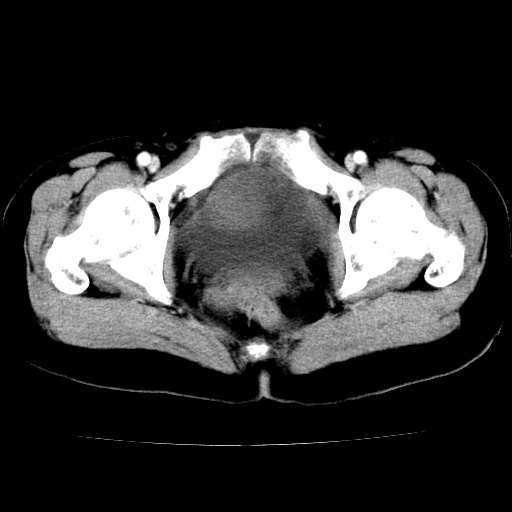

标题: CT24785:女,62岁,发现下腹部肿物半年。 [打印本页]

标题: CT24785:女,62岁,发现下腹部肿物半年。

女,62岁,发现下腹部肿物半年,下腹部不适。

考虑回肠间质瘤,不排除卵巢癌可能。

支持卵巢癌

该年龄性别首先考虑平滑肌肉瘤可能性大,其他待排除。